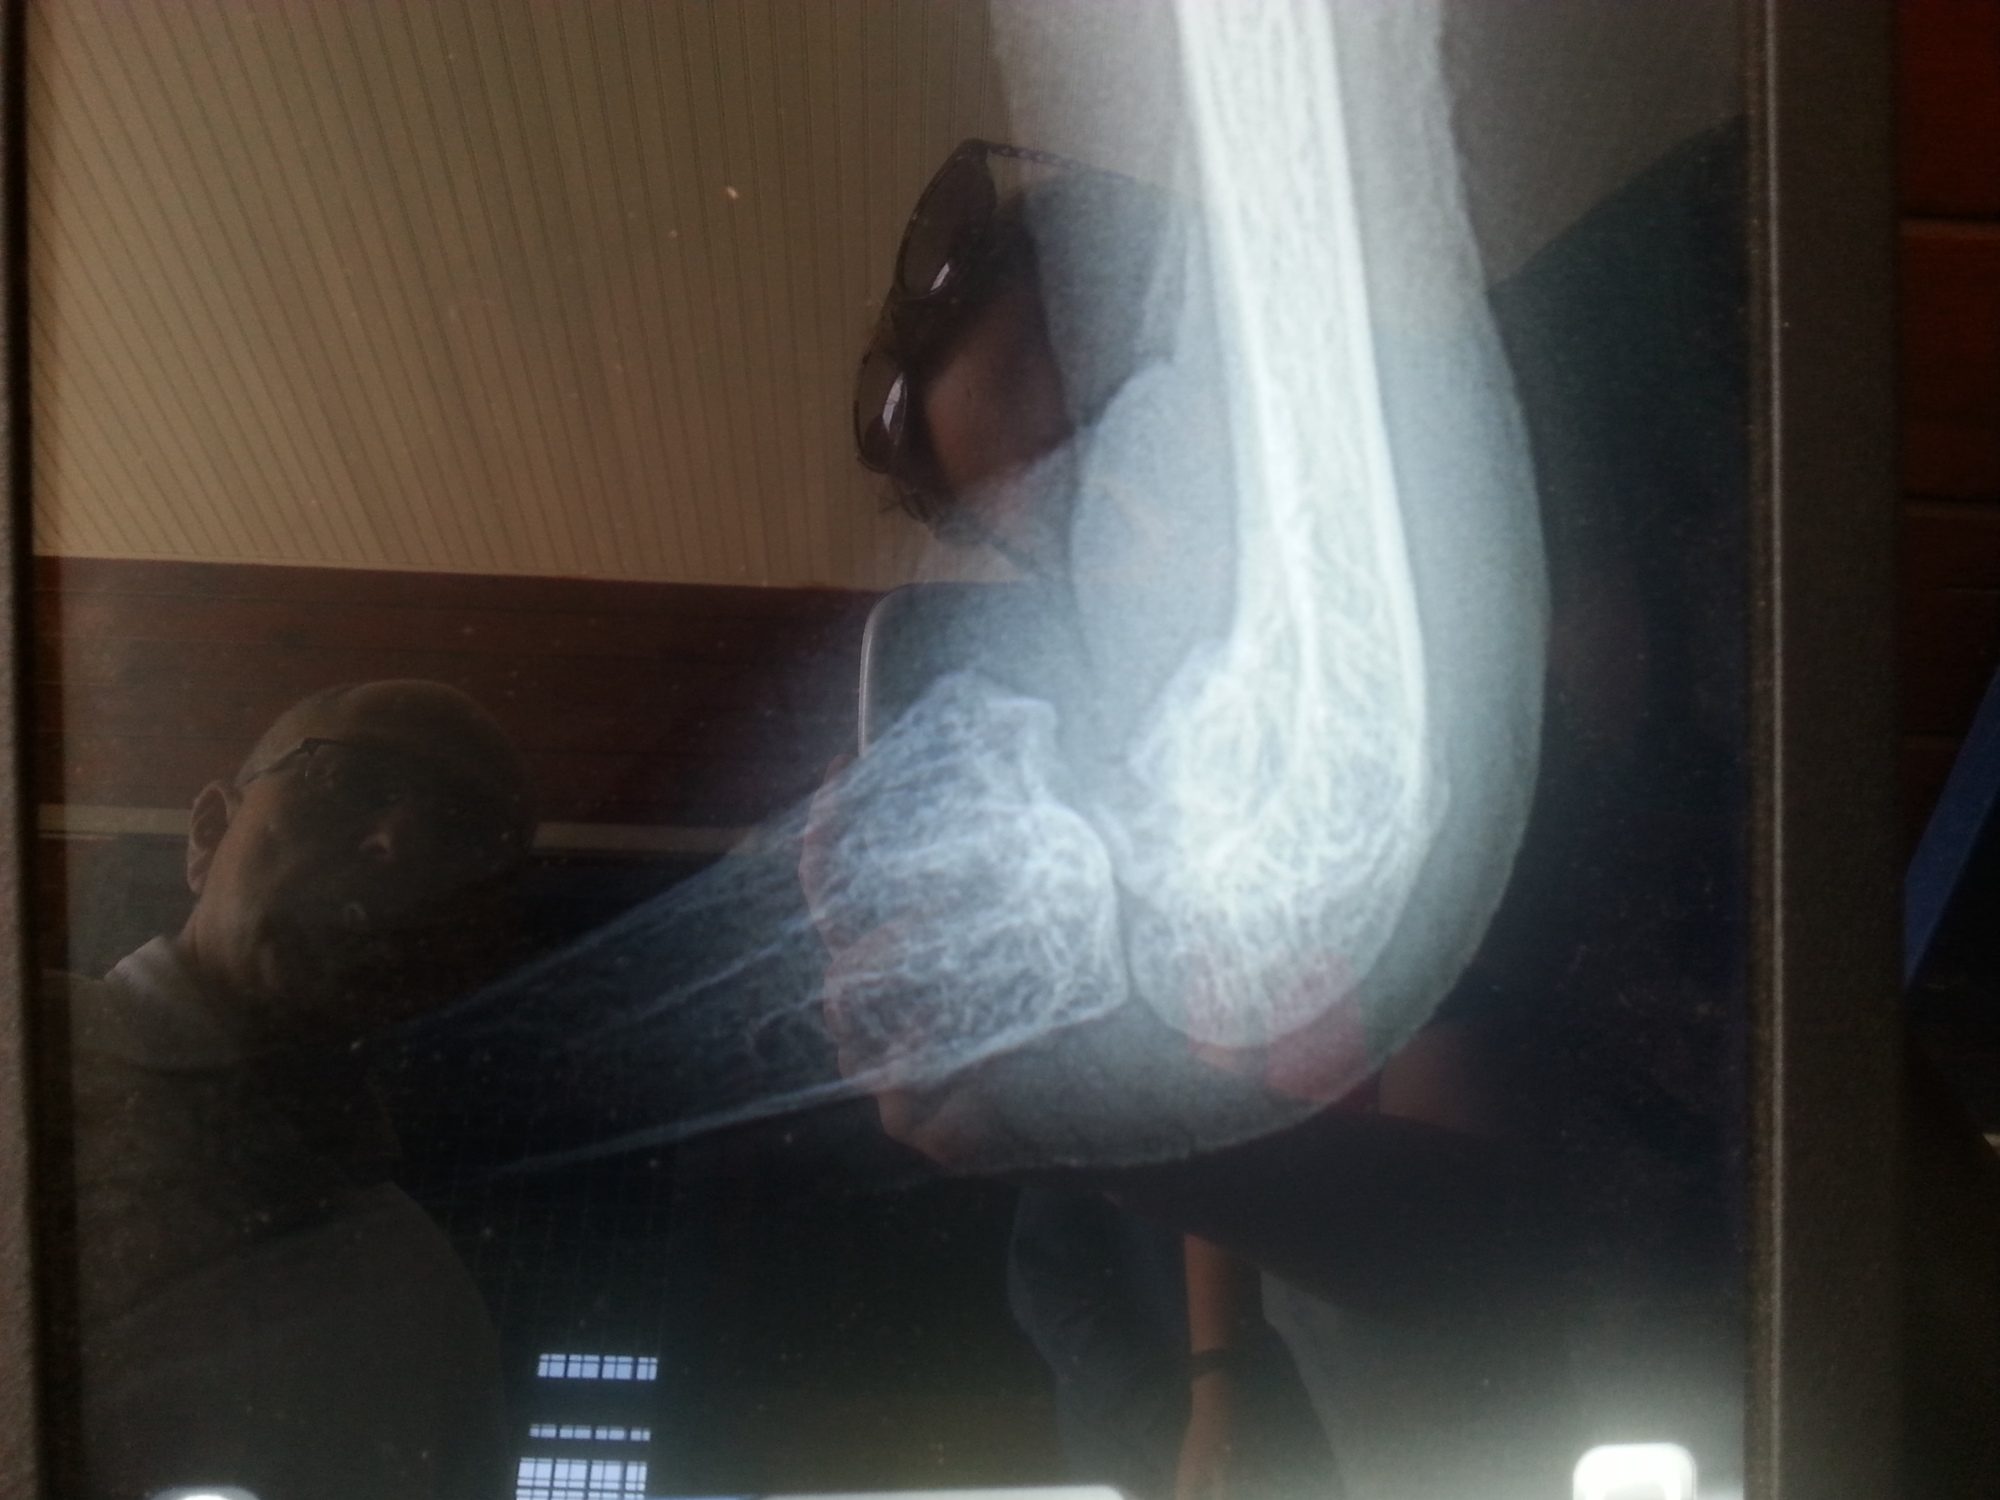

I think that if this were a new break, there would be more options for treating the leg. When she was younger and gimping around quickly, I assumed at that point the injury was old and she would just walk with a gimp. When it got really bad 2 weeks ago, I got really worried. She is a big bird and gaining weight quickly so I thought the extra weight was putting too much strain on her leg. After 2 weeks of oxytetracycline, she is now back to a regular gimp.